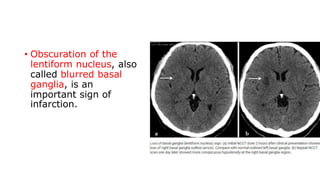

• Obscuration of the

infarction.

• Obscuration ofthe lentiform nucleus, also called blurred basal ganglia, is an important sign of infarction.